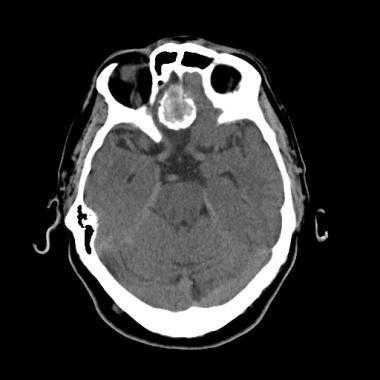

З адняя тенториальная менингиома на корональном КТ-изображении с контрастным усилением. К намету мозжечка прилежит объемное образование повышенной плотности с четкими краями. Визуализируются застой спинно-мозговой жидкости, легкий отек прилежащих тканей, гомогенный характер контрастирования, а также расширение желудочков.